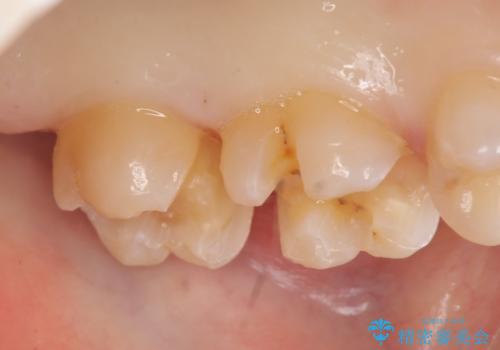

左上7近心の虫歯は歯茎より深く、歯茎を下げるため歯周外科を行いました。

術後歯肉の回復を待ち、左下6、7ともにセラミックインレーによる修復を行いました。

歯茎より深い虫歯の治療について

虫歯が進み歯茎より深くなってしまうと、虫歯を取り残してしまうリスク、樹脂の硬化の妨げ、補綴物の不適合、歯肉炎・歯周病のリスクの増大等様々な弊害が起こり得ます。

そのため当院では歯周外科手術(歯茎を下げる手術)や歯の挺出による、虫歯が歯茎より深いという問題の解決を推奨しております。